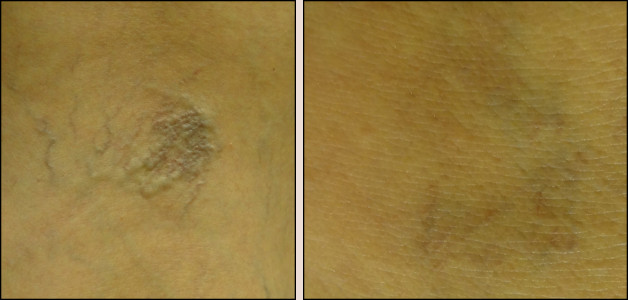

laser vein removal

44-year-old European fair-skinned female before and 3 months after removal of leg hemangioma with 3 laser treatments. This is a benign vascular tumor. The laser clots off the blood flowing through this tumor, and then your body gets rid of it. You might need multiple treatments because the vessels can re-open up again. This lesion can also be removed with cauterization, shaving or excision, but laser has the best result with minimal chance of scarring.